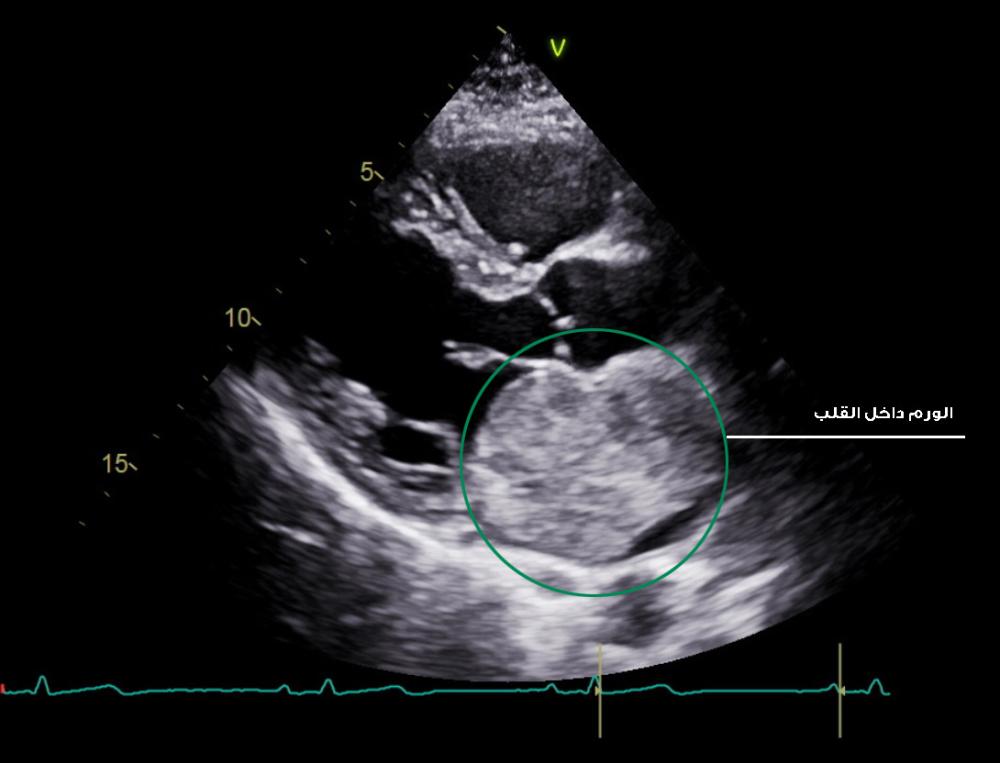

وأوضح مدير عام المركز الدكتور إبراهيم الصبحي، أنه تم استقبال المريض البالغ من العمر 48 عاماً عبر نظام «إحالتي» من منطقة تبوك وهو يعاني ضيقًا في التنفس، وهبوطًا في ضغط الدم، وعند إجراء فحص القلب بالموجات فوق الصوتية وعمل قسطرة للشرايين التاجية تبين وجود كتلة كبيرة الحجم داخل الأذين الأيسر ملتصقة بالحاجز الفاصل بين الاذين الأيسر والأيمن.

وعلى الفور تطلبت حالته التدخل الجراحي السريع للحفاظ على حياته وتفاديًا للمضاعفات التي يمكن أن تنجم عن هذه الكتلة تم إدخاله لغرفة العمليات واستأصل الورم بنجاح الذي بلغ حجمه بـ(7 سم x 5 سم ) تقريباً.